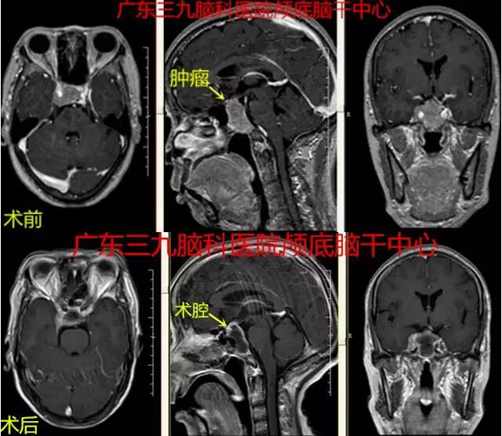

经神经外科专家会诊检查,发现导致梁女士视力下降的元凶是脑子里长了垂体瘤”。入院后完善相关检查,CT显示垂体瘤,行内镜下经鼻蝶大垂体瘤切除术,术程顺利,肿瘤全切除。术后病理报告示:垂体腺瘤。

▲图3:2017-12-03 术前MR示鞍区(鞍底为主)一团块状稍长T1不匀长T2、FLAIR序列呈稍高信号影,范围约3.6cm×1.7cm×2.8cm,增强后呈不均匀轻度-中等度强化;斜坡受累,右侧颈内动脉海绵窦段受包绕。术前术后磁共振对比肿瘤切除